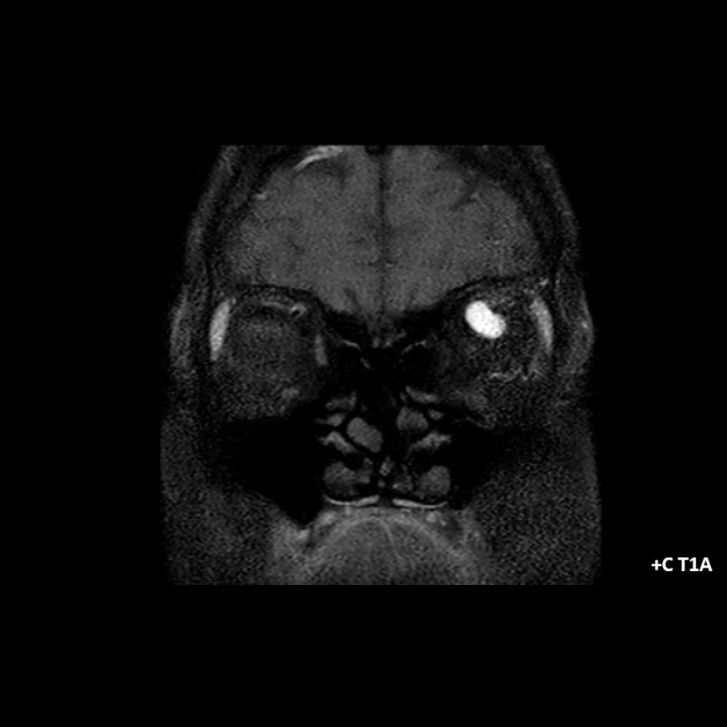

- A) Orbital MRG’de yağ baskılı T2A görüntülerde sol orbital globta ekzoftalmus (ok) izlenmiş olup retrobulbar yağlı dokuda kirlenmeler (ok) ve dilate superior oftalmik ven (ok) dikkati çekiyor. Beyin MRG’de kontrastlı T1A görüntüde sol kavernöz sinüste simetriğine oranla genişleme (ok) izleniyor.

- B) Pre ve post-kontrast yağ basklılı T1A görüntüler incelendiğinde superior oftalmik venin (oklar) kontrast madde verildikten sonra homojen dolum gösterdiği, dilate ve tortiyoze görünümde olduğu izleniyor.

- BT ve MRG: Propitozis, ekstraokuler kaslarda genişleme, superior oftalmik vende genişleme ve tortiyozite, ipsilateral kavernöz sinüste genişleme gösterilebilir. Serebral venöz konjesyonu olan ve intrakraniyal basınçları yükselen hastalarda serebral ödem, hemoraji, leptomeningeal ve kortikal venlerin dilastasyonunu görülebilir. Bunlara ek olarak travmaya sekonder olgularda BT ile eşlik eden fraktürler gösterilebilir.